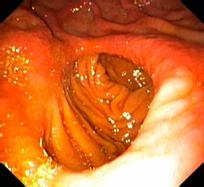

其次,多个疣状、突起和像丘疹一样的隆起可能会在患者的胃粘膜上发生,并且中间一般有程度严重的糜烂而周围会有泛红和大小相仿的呈红色的斑点,一般在胃窦部位容易发生。